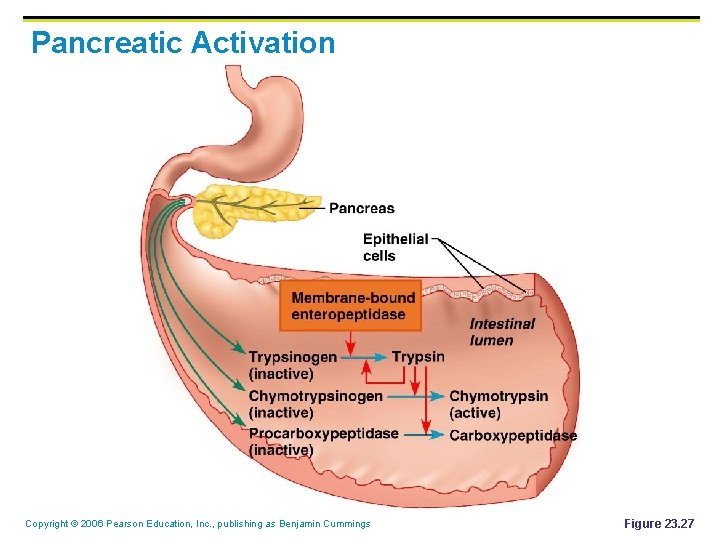

Pancreas § Location § § Lies deep to the greater curvature of the stomach The head is encircled by the duodenum and the tail abuts the spleen Copyright © 2006 Pearson Education, Inc. , publishing as Benjamin Cummings

Pancreas § Exocrine function § § Secretes pancreatic juice which breaks down all categories of foodstuff The pancreas also has an endocrine function – release of insulin and glucagon (hormones) Copyright © 2006 Pearson Education, Inc. , publishing as Benjamin Cummings

Pancreatic Activation Copyright © 2006 Pearson Education, Inc. , publishing as Benjamin Cummings Figure 23. 27